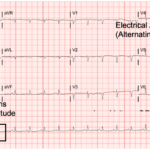

Cardiac tamponade is a rare and life-threatening condition that can be caused by trauma and various medical conditions. Failure to recognize and repair it quickly could lead to significant morbidity or even death. This case demonstrates the electrocardiogram (ECG) findings of low voltage QRS and electrical alternans in cardiac tamponade. It also highlights the classic ultrasound (US) findings of pericardial effusion and right ventricular collapse during diastole in cardiac tamponade. Classic physical exam findings of cardiac tamponade include Beck’s Triad (jugular venous distention, hypotension, and muffled heart sounds) and pulsus paradoxus. This patient only had jugular venous distention and pulsus paradoxus. The case is centered on a 52-year-old male who presented with shortness of breath, wheezing, and a productive cough with streaks of blood. A CT chest was performed which revealed a large pericardial effusion, right upper lobe lung mass, and bilateral pulmonary emboli. A bedside transthoracic echocardiogram was then performed which confirmed the large effusion as well as right ventricular collapse during diastole. Cardiothoracic surgery and interventional cardiology were consulted and both agreed to take the patient to the cardiac catheterization lab for percutaneous drainage of the effusion. Pericardiocentesis was performed and 1.7 liters of serosanguinous fluid was removed and a drain was left in place. He recovered well from the procedure and had an uneventful admission. After reviewing this case, learners should be able to recognize the diagnostic features and various causes of pericardial effusion and cardiac tamponade.

Electrocardiography, echocardiography, cardiac tamponade.